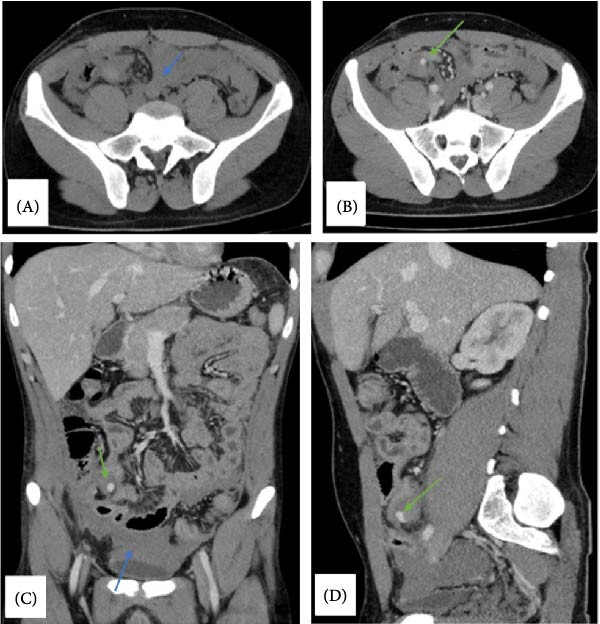

УЗИ брюшной полости показало диффузное увеличение толщины стенки тонкой кишки, преимущественно в области правого квадранта, значительное повышение эхогенности жировой ткани и наличие свободной жидкости в малом тазу с гиперэхогенными включениями. Также в стенке терминального отдела подвздошной кишки был выявлен небольшой участок гиперэхогенности. КТ брюшной полости и таза с контрастированием показала гемоперитонеум с экстравазацией в месте аппендэктомии (рис. 1).

Рисунок 1. КТ-снимки брюшной полости в аксиальной (A, B), коронарной (C) и сагиттальной (D) плоскостях, показывающие умеренное количество свободной жидкости (гемоперитонеум), преимущественно в правой подвздошной ямке (синяя стрелка); также в месте удаленной культи аппендикса отмечена очаги гиперинтенсивного сигнала, которые могут указывать на перитонеальное кровотечение (зеленая стрелка).

У пациента были симптомы, которые могли маскироваться под послеоперационные осложнения: генерализованная боль в животе, которая вначале имела локальный характер, высокая температура и усиление боли в месте операции. Анамнез недавней аппендэктомии мог осложнить диагностику, так как аппендицит культи обычно развивается через несколько месяцев или лет после операции. Аналогично, УЗИ и КТ показали признаки воспаления, возможно, инфекционной природы (утолщение стенок тонкой кишки, повышение эхогенности, наличие свободной жидкости и гемоперитонеума). Вместе с этим, повышение уровня нейтрофилов и наличие очага гиперэхогенности в терминальном отделе подвздошной кишки могли указывать на воспаление в месте культи аппендикса. Также КТ-признаки экстравазации в зоне операции свидетельствовали о кровотечении и одновременно затрудняли поиск культи. Диагностическая лапаротомия выявила наличие гнойного экссудата и остатки аппендикса, что позволило поставить диагноз аппендицита культи. Послеоперационное гистологическое исследования подтвердило наличие воспаленной ткани аппендикса с трансмуральной инфильтрацией нейтрофилов.